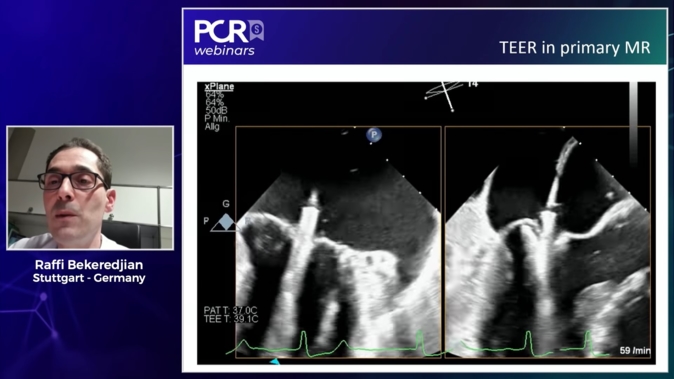

M-TEER for primary mitral regurgitation

08 Feb 2025 – From PCR Tokyo Valves 2025

In this PCR Tokyo Valves 2025 session on M-TEER for primary mitral regurgitation, gain valuable insights starting with an overview of current TEER devices. Benefit from four case studies that highlight the features of these devices, explore strategies to prevent mitral regurgitation recurrence post-TEER, and delve...